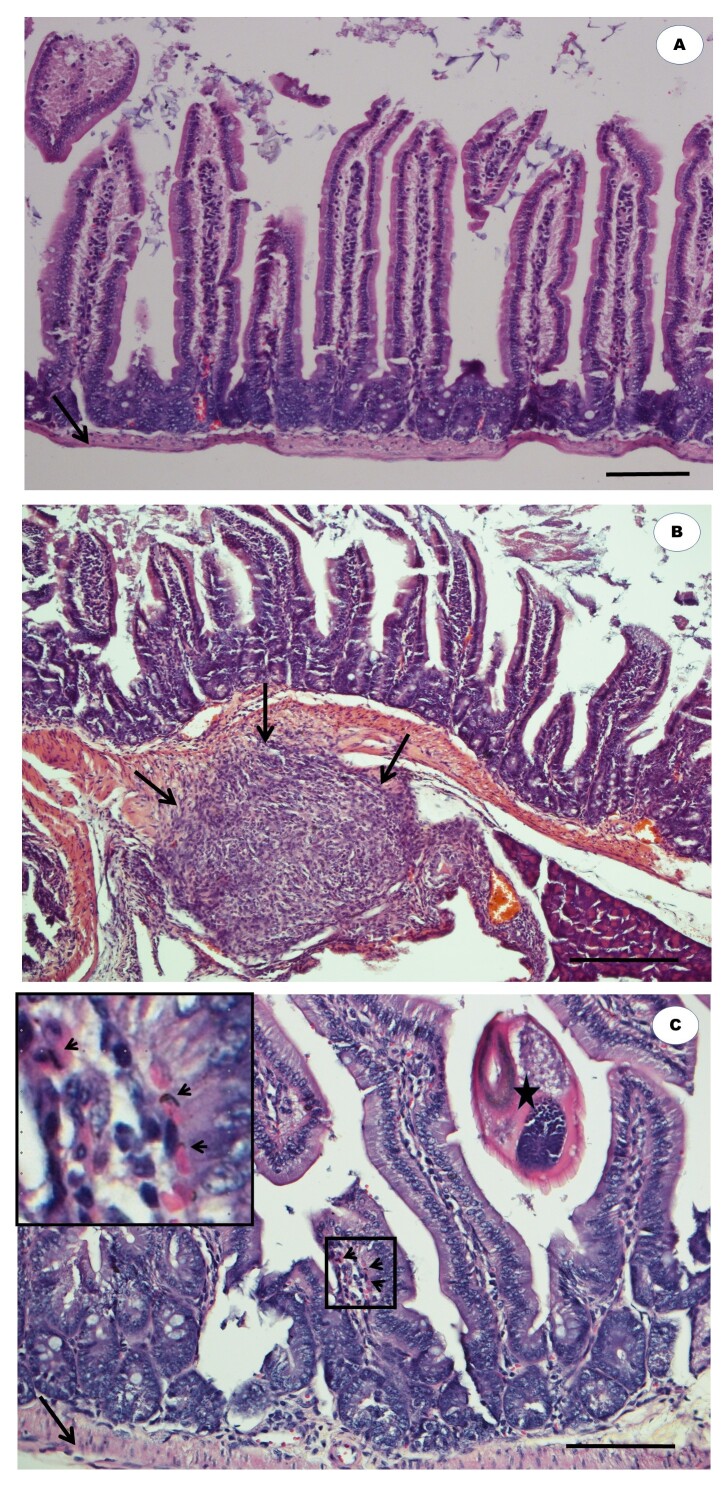

本文报道了一种新的柠檬草的体内研究,以评估其驱虫活性。为此,将C57BL/6小鼠分为三组:G1组:未感染;G2:阴性对照,感染多回螺旋体,给予3%二甲亚砜(DMSO);G3组:多回红僵菌感染,柑桔水提液(50mg/kg)处理。采用灌胃的方法,对大鼠进行解剖和脏器切除后的解剖组织病理学评价。此外,还评估了每克粪便中的卵数(epg)和每只动物小肠中成虫的数量,以及血细胞计数。体内实验显示,柑橘酸杆菌治疗小鼠的epg(54%)、成虫数量(89%)、嗜酸性粒细胞数量和肠道病变减少。这些结果表明,在这里评估的剂量下,柑橘的粗水提取物具有驱虫和可能的抗炎特性,因为它对胃肠道多回线虫和受损组织的恢复有效。因此,这种植物显示出控制胃肠道线虫的潜力。

This paper describes a novel in vivo study of Cymbopogon citratus (lemon grass) to assess its anthelmintic activity. To this end, C57BL/6 mice were separated into three groups: G1: uninfected; G2: negative control infected with Heligmosomoides polygyrus bakeri and administered with 3% dimethyl sulfoxide (DMSO); and G3: infected with H. polygyrus bakeri and treated with C. citratus aqueous extract (50mg/kg). The extract and H. polygyrus bakeri were administered via gavage and the anatomo-histopathological evaluation of the animals took place after necropsy and organ removal. In addition, the number of eggs per gram of feces (epg) and of adult parasites in the small intestine of each animal, as well as blood cell counts, were assessed. The in vivo assay revealed a reduction in the epg (54%), number of adult nematodes (89%), number of eosinophils, and intestinal lesions in mice treated with C. citratus. These results suggest that the crude aqueous extract of C. citratus at the dose evaluated here has anthelmintic and possibly anti-inflammatory properties, given its effectiveness against gastrointestinal H. polygyrus bakeri nematodes and the recovery of damaged tissues. Therefore, this plant shows potential to control gastrointestinal nematodes.